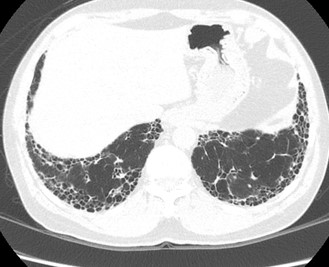

Figura 2. A e B: Paciente com artrite reumatóide e padrão de pneumonia intersticial usual (PIU). Controle de 4 anos (B) não evidencia progressão significativa das alterações.

A proporção exata de pacientes com doença intersticial pulmonar não FPI que podem desenvolver FPP não é conhecida(1), porém alguns achados radiológicos, podem ajudar a prever progressão da doença intersticial. A presença de cistos de faveolamento e bronquiectasias de tração, por exemplo, se relacionam com prognósticos clínicos piores, assim como extensas alterações fibróticas são consideradas preditor de mortalidade em pacientes com FPI, doença intersticial relacionada a artrite reumatoide, esclerose sistêmica, pneumonite por hipersensibilidade com fibrose, sarcoidose e doenças intersticiais pulmonares não classificadas(5).